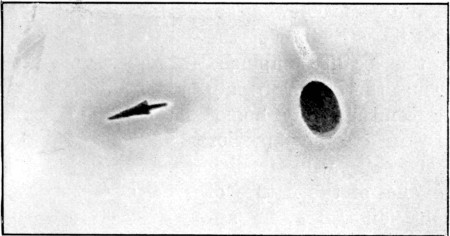

19. Oval Entry, Starred Exit Wounds58

20. Circular Entry, Slit Exit Wounds59